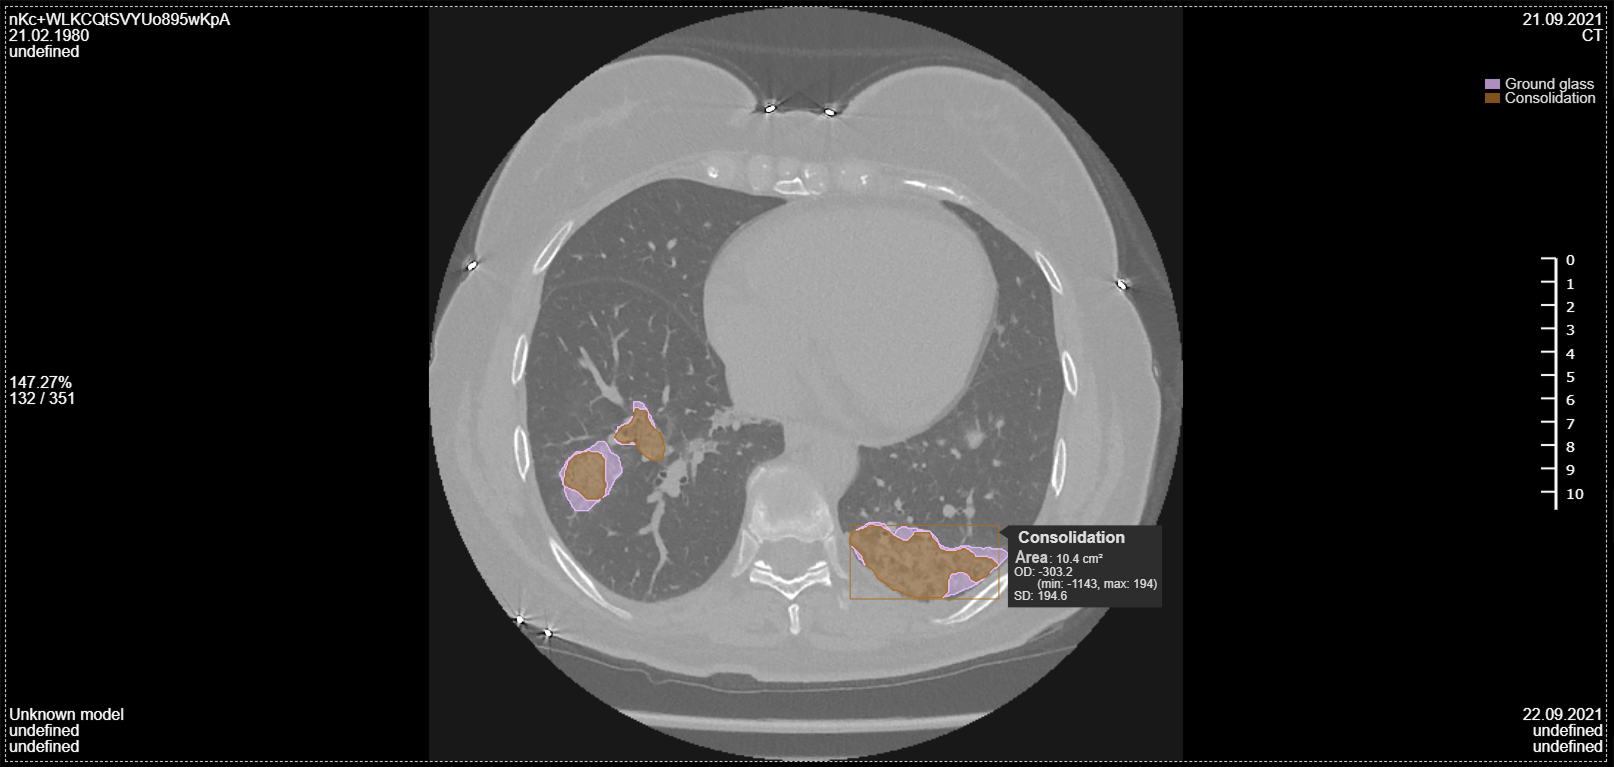

• Classifies nodules, masses, and pneumonia indicators for precise analysis

• Localizes pathologies with visual annotations on CT images